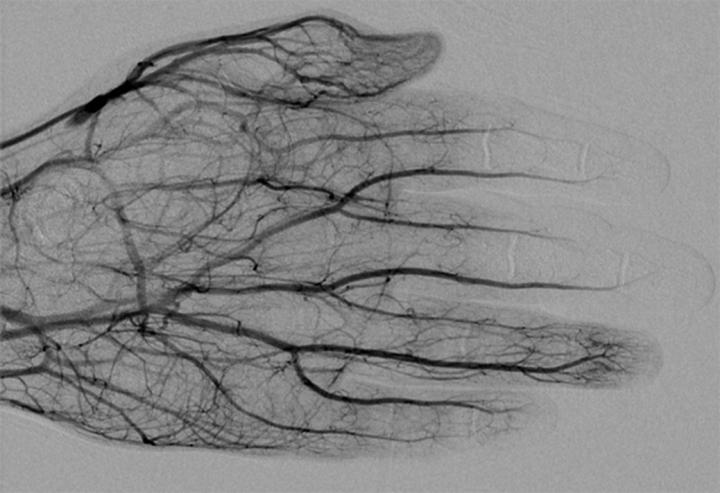

image: DSA image obtained approximately 24 hours after 1 mg/h IA tPA infusion, 500 U/h heparin via peripheral IV, and daily oral aspirin (81 mg) shows improved perfusion of digital arteries, albeit with suboptimal vascular blush of distal second and third phalanges.

Lee and Higgins' analyzed series included 209 patients with 1109 digits at risk of amputation treated with IA or IV tPA--116 and 77 patients, respectively. A total 926 at-risk digits were treated with IA tPA and resulted in amputation of 222 digits, for a salvage rate of 76%. Twenty-four of 63 patients underwent amputation after IV tPA, resulting in a 62% salvage rate.

Both digital subtraction angiography (DSA) and triple-phase bone scan were utilized for initial imaging evaluation of patients with severe frostbite injuries.